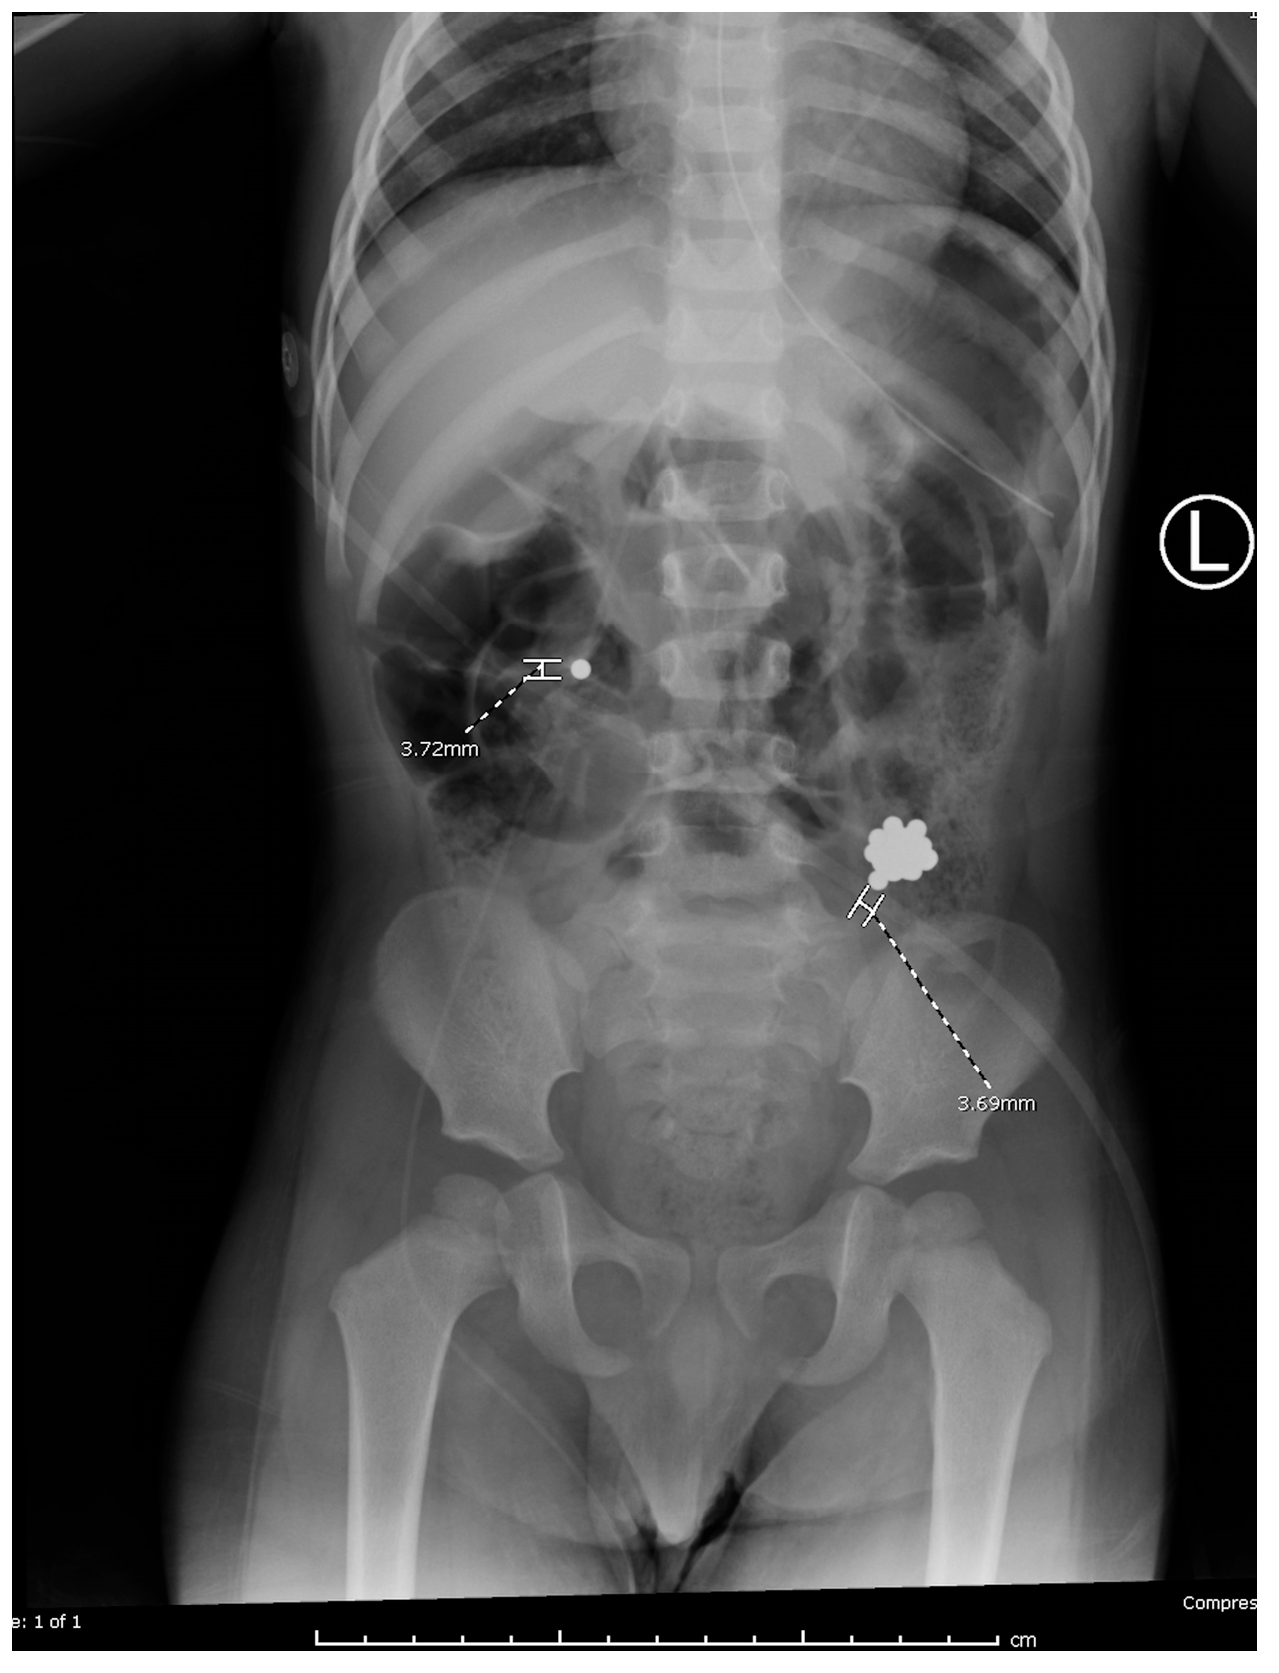

Colonoscopy was attempted by pediatric gastroenterology in an unprepped colon to avoid procedural delays. Due to formed stool, retrieval was unsuccessful. A nasogastric tube was placed for MiraLAX-based bowel prep, and serial abdominal x-rays were performed (Figure 4a,b). This approach aligns with conservative management strategies reported in the literature [3,11].

Figure 4. Abdominal radiographs before (a) and after (b) colonoscopy.